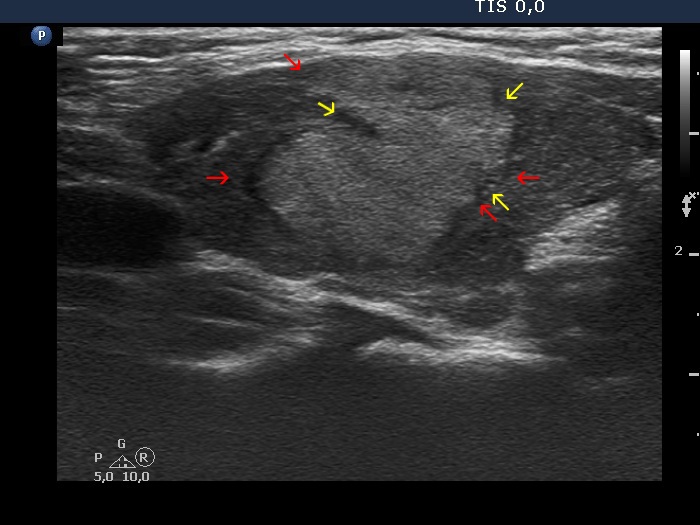

The borders of the nodule - case 479 (ultrasonographic picture 4)

Left lobe, longitudinal view. The lesion has irregular, lobulated surface caused by the infiltration of the underlying thyroiditis. The primary event is the lymphocytic infiltration (yellow arrows), while the protrusions (red arrows) are only the consequence of the former.